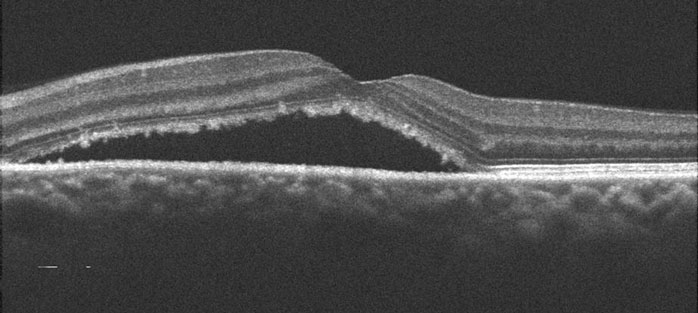

You can’t diagnose CSR by looking in the mirror since your eye will usually look and feel normal. The diagnosis is made with a thorough retinal examination through a dilated pupil, along with OCT scanning and fluorescein angiography. Angiography is helpful in confirming the diagnosis, as well as in identifying the leak when contemplating treatment.

The hallmark clinical finding of CSR consists of one or more “blisters” of fluid (serous detachment) beneath the macula. The vast majority of blisters will resolve spontaneously within 3 to 4 months. Vision usually returns to normal, although many patients are left with subtle changes in their central or color vision. Patients will often develop recurrent leaks in one or both eyes over the years.